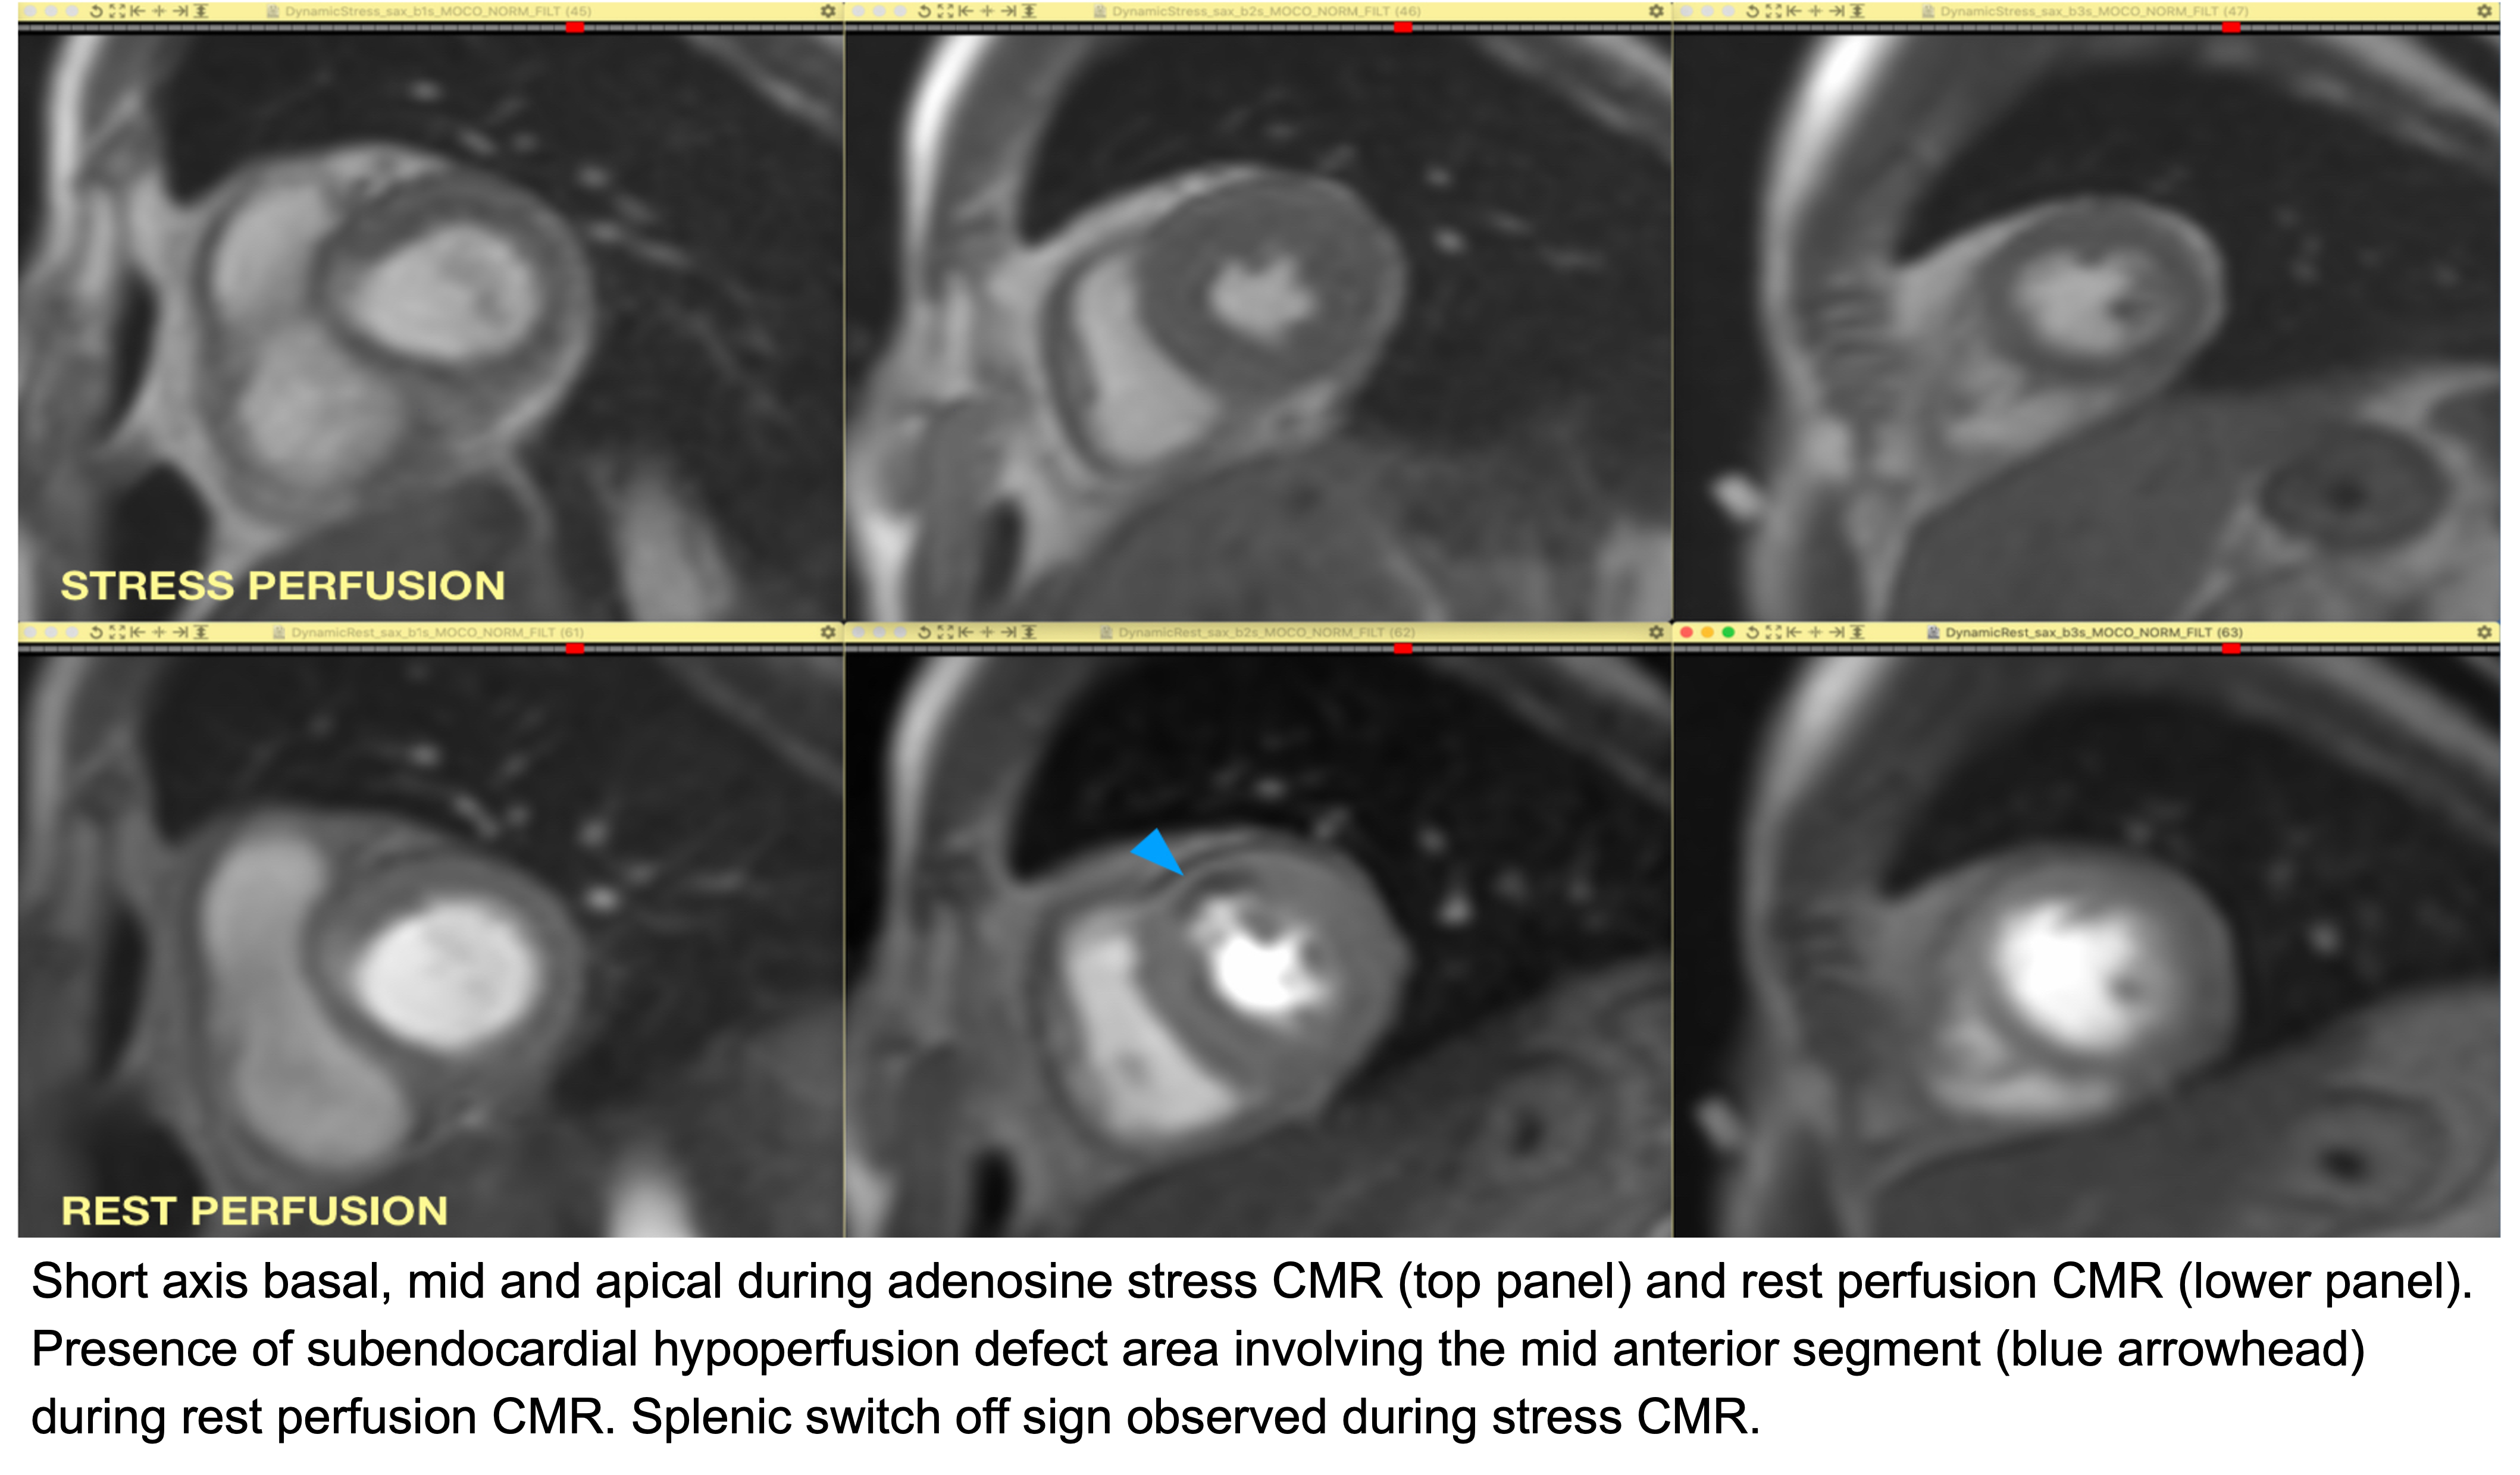

Cardiac magnetic resonance imaging (CMR): rest perfusion CMR demonstrated a mid-anterior hypoperfusion defect, consistent with adenosine-induced coronary vasospasm.

Our patient had severe angina with hypertensive urgency during adenosine stress cardiac magnetic resonance imaging (CMR), which resolved with supportive care. Adenosine is a potent coronary vasodilator commonly used in stress CMR and fractional flow reserve (FFR) evaluation. While typically safe, paradoxical coronary vasospasm is an uncommon but significant event, particularly in patients with endothelial dysfunction or variant angina. Proposed mechanisms include rebound vasoconstriction, sympathetic activation, and impaired endothelial response. Recognition is challenging as symptoms may mimic acute coronary syndrome, yet rapid identification and treatment are crucial to avoid adverse outcomes.